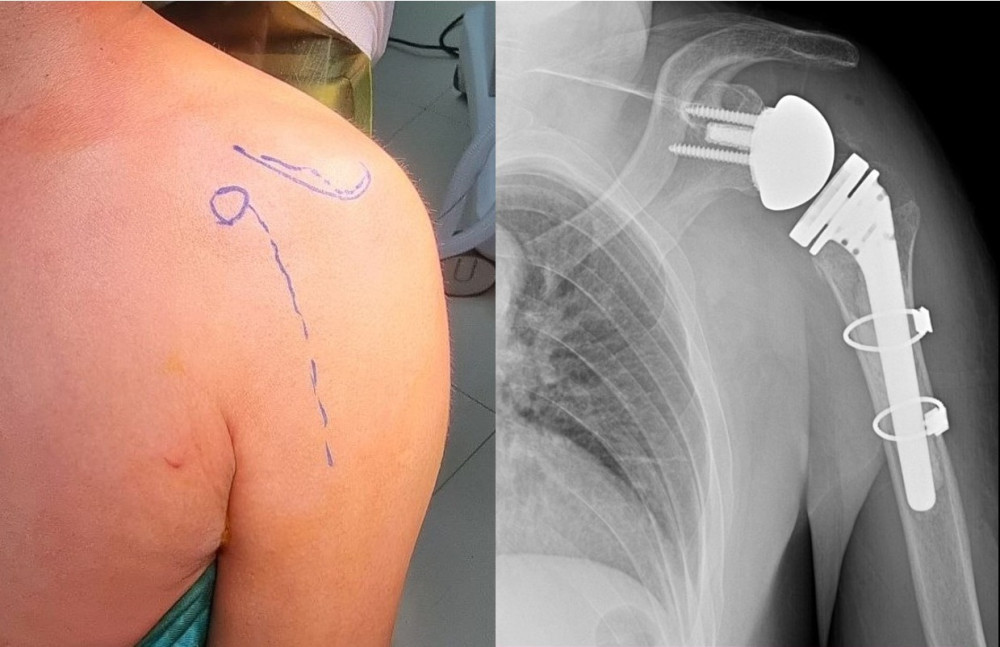

Гэмтэл согог судлалын үндэсний төвийн Гар сарвууны мэс заслын тасгийн хамт олон Монгол Улсад анх удаа мөрний үеийг бүтэн солих мэс заслыг амжилттай хийж, эмчилгээний шинэ технологи нэвтрүүлжээ. ГССҮТ-ийн 2023 оны статистик мэдээллээс үзвэл, Яаралтай тусламжийн тасагт 168 мянга орчим хүн үйлчлүүлсний 34 хувь буюу 57.626 нь гар сарвуу дээд мөчний гэмтлийн тусламж үйлчилгээ авсан байна. Үүнээс 3948 хүн хэвтэн эмчлүүлсэн бөгөөд 3575 нь мэс засал эмчилгээ хийлгэжээ.

Гар сарвууны мэс заслын тасагт дээд мөчний хугарал, мултрал, дээд мөчний үе солих мэс засал, мөчдийн судас, мэдрэл, шөрмөсний гэмтлийн мэс засал, тасарсан мөч эргүүлэн залгах, яс зөөлөн эдийн дутмагшлыг нөхөн сэргээх бичил мэс заслаас гадна төрөлхийн болон олдмол согог засах мэс засал, мөчдийн яс, зөөлөн эдийн хавдар, үрэвслийн мэс заслын тусламж үйлчилгээг олон улсын түвшинд үзүүлж байна.

| Мөрний үеийг бүтэн солих мэс заслын эмчилгээг Монголд нэвтрүүлжээ |